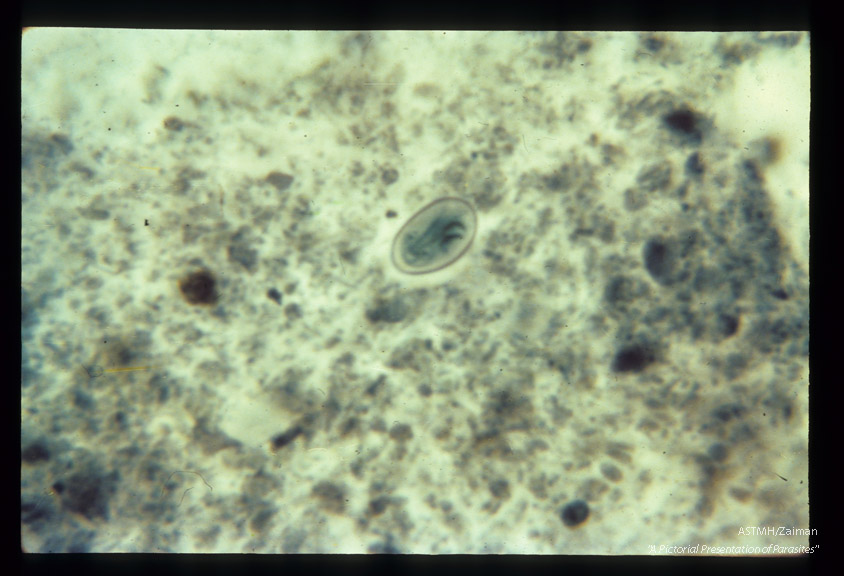

Cyst in stool. Chlorazol black stain.

Giardia lamblia

Description: Cyst in stool. Chlorazol black stain.